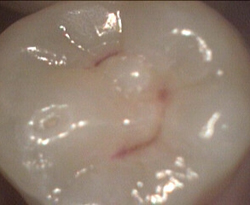

failed sealant has decay restored with white filling

old leaky sealant and decay restored